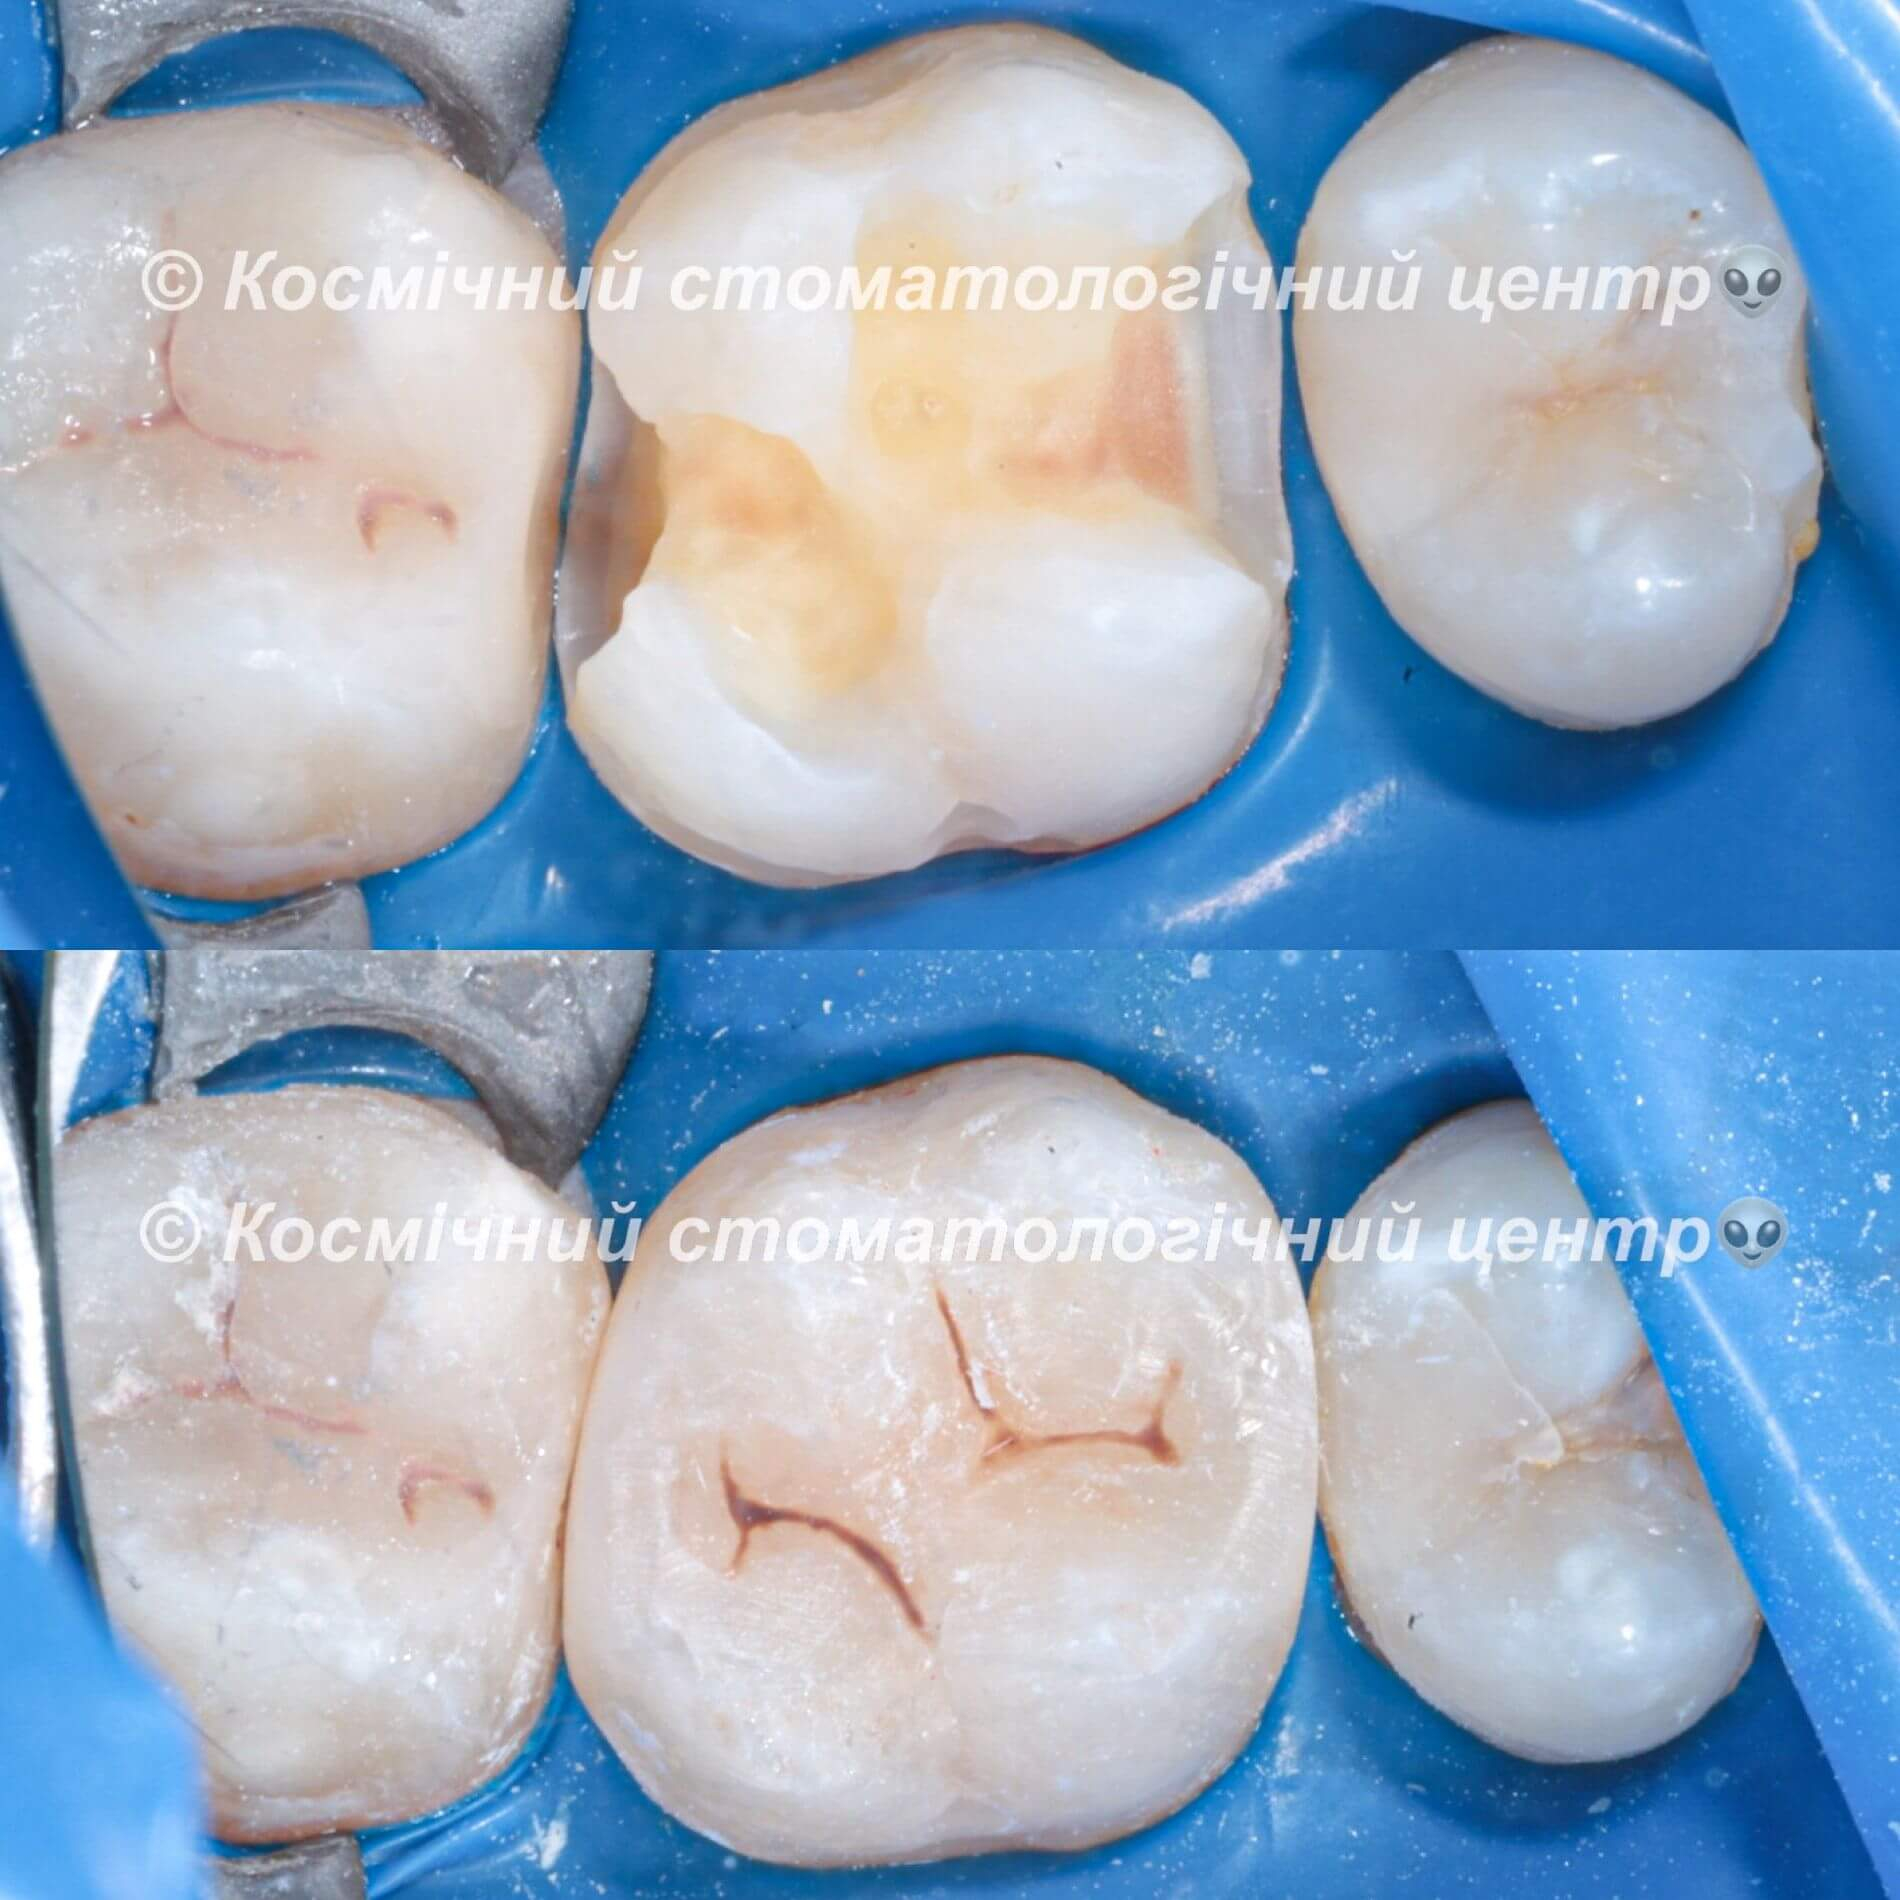

Пломбування зубів - процедура доволі земна та стандартна. Зубна порожнина заповнюється пломбувальним матеріалом та здійснюється відновлення анатомічної форми зуба. Завдяки цьому нам вдасться зберегти твій зуб і запобігти поширенню шкідливих бактерій вглиб зубу та далі по ротовій порожнині. Встановлення пломби - це оптимальний спосіб лікування карієсу і фінальний етап лікування пульпіту. Процес пломбування зуба відрізнятиметься в залежності від техніки та призначення пломби.

Колись давним-давно, в земних стоматологіях ставили цементні пломби. Думаємо, цей незабутнє відчуття «піску» після процедури багатьох переслідує досі. На щастя, ці часи минули, і тепер для твоїх зубів нас є крутий фотополімерний матеріал з космічними наночастинками. Він не тільки дуже міцний, а й гарно світиться ночами(це звісно ж жарт). Це просто найінноваційніший пломбувальний матеріал з усіх, що існуюють на ринку.

- Постійні. В Космічній стоматології Драганчука ми застосовуємо дуже крутий пломбувальний матеріал з наночастинками. За міцністю він не поступається найміцнішим метеоритам нашої галактики, тож відмінно витримує значні жувальні навантаження. Ще один особливо важливий момент - відмінні естетичні характеристики, що дозволяє ставити такі пломби не лише в жувальній зоні, а й на передній зубах.

- Кращі фотополімерні матеріали з наночастиками: пломба ідеально пасуватиме за кольором, формою, міцністю.

Лікування зубів у Космічній стоматології Драганчука передбачає використання інноваційних фотополімерних матеріалів з наночастинками. Ці матеріали дозволяють проводити лікування зубів малоінвазивно, точно, надійно і довговічно. Пломба ідеально пасує по кольору, формі та міцності.

Галерея